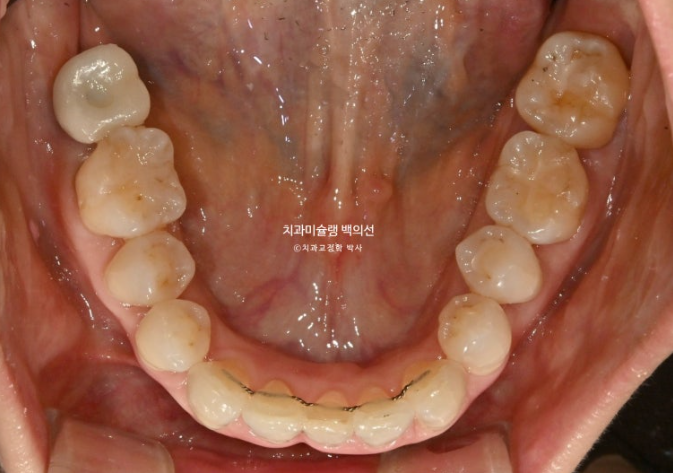

50대 발치교정 소개해드릴 압구정 인비절라인 치과 입니다.

1년 전 치아 틀어짐이 점점 심해지면서 찾아오신 50대 환자분

예전에는 입이 편하게 다물어졌었는데 치아가 틀어지고 벌어지고 내려오면서 이제는 입이 편하게 안 다물어지는 것도 불편한 상태입니다.

파란 화살표 치아는 잇몸이 검붉게 보입니다.

엑스레이상 이미 치주염이 상당히 진행이 되어 발치가 불가피한 상황이였습니다.

위 앞니는 잇몸이 꽉 잡아주지를 못해서 점점 솟아 내려오고 튀어나오면서 치아사이가 벌어졌습니다.

작은어금니도 안으로 쓰러져 있어서 이 부분은 윗니와 엇갈려 물리는 가위교합 입니다.